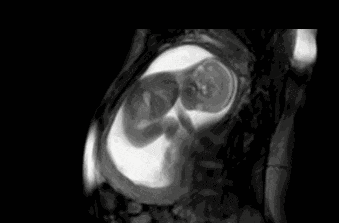

第2张图:用身体感受子宫

随着宝宝长大,子宫空间相对变小,活动时容易触碰到子宫壁。有时候,妈妈甚至能看到肚皮被小脚、小手或小头顶出一个小鼓包。

宝宝正是通过身体与子宫的接触,建立与妈妈最早的亲密连接。这也是为什么妈妈和孩子感情特别深——十个月的血脉相连,早已心意相通。